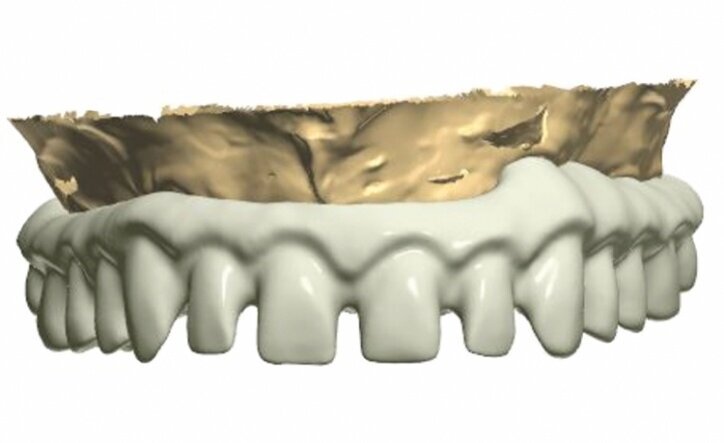

The model was scanned while the abutments were made ready in such a way that they could serve as telescopic crowns, also in the final stage (Fig. 9). Primary and secondary telescopic crowns were designed on the abutments (Figs. 10 & 11) on the assumption that secondary crowns had been made ready twice, that is, for the sake of temporary prosthesis and at the same time for gluing it into the final construction (Figs. 12 & 13). Abutments were mounted on implants by means of Pattern Resin (Figs. 14 & 15) in such a way that the position does not change during mounting.